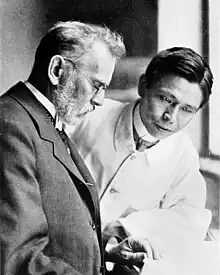

As a model for experimental therapy Ehrlich used a guinea pig disease trypanosoma and tested out various chemical substances on laboratory animals. The trypanosomes could indeed be successfully killed with the dye trypan red. Beginning in 1906, he intensively investigated atoxyl and had it tested by Robert Koch along with other arsenic compounds during Koch's sleeping sickness expedition of 1906/07. Although the name literally means "nonpoisonous", atoxyl does cause damage, especially to the optic nerve. Ehrlich elaborated the systematic testing of chemical compounds in the sense of screening as now practiced in the pharmaceutical industry. He discovered that Compound 418 - Arsenophenylglycine - had an impressive therapeutic effect and had it tested in Africa.

With the support of his assistant Sahachiro Hata Ehrlich discovered in 1909 that Compound 606, Arsphenamine, effectively combatted "spirillum" spirochaetes bacteria, one of whose subspecies causes syphilis.[18] The compound proved to have few side effects in human trials, and the spirochetes disappeared in seven syphilis patients after this treatment.

After extensive clinical testing (all the research participants had the negative example of tuberculin in mind) the Hoechst company began to market the compound toward the end of 1910 under the name Salvarsan. This was the first agent with a specific therapeutic effect to be created on the basis of theoretical considerations. Salvarsan proved to be amazingly effective, particularly when compared with the conventional therapy of mercury salts. Manufactured by Hoechst AG, Salvarsan became the most widely prescribed drug in the world. It was the most effective drug for treating syphilis until penicillin became available in the 1940s.[19] Salvarsan required improvement as to side effects and solubility and was replaced in 1911 with Neosalvarsan. Ehrlich's work illuminated the existence of the blood-brain barrier, although he himself never believed in such a barrier, with Lina Stern later coining the phrase.